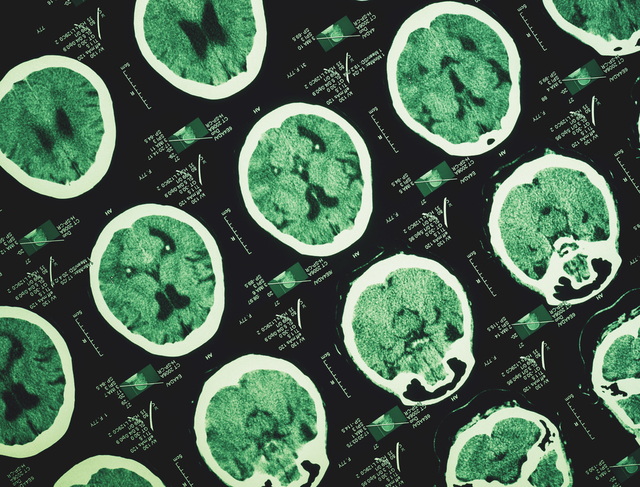

Tanıda ileri görüntüleme yöntemlerinin kullanıldığını belirten Doç. Dr. Danışan, “MR anjiyografi, BT anjiyografi ve gerektiğinde DSA (Dijital Subtraksiyon Anjiyografi) ile yüksek doğruluk oranıyla beyin anevrizması tanısı koyabiliyoruz. Açık cerrahi yöntemler ve anjiyografi yöntemi ile uygulanan endovasküler tedaviler mevcut. Günümüzde dünyada en sık tercih edilen ve güncel yaklaşım endovaskülertedavilerdir. Özel iplikçikler ve beyin damarları için üretilmiş stentler kullanarak anjiyografik yöntemlerle anevrizmaları tedavi ediyoruz. Bu sayede kısa yatış süresi ve yüksek teknik başarı elde edilebiliyor” dedi.